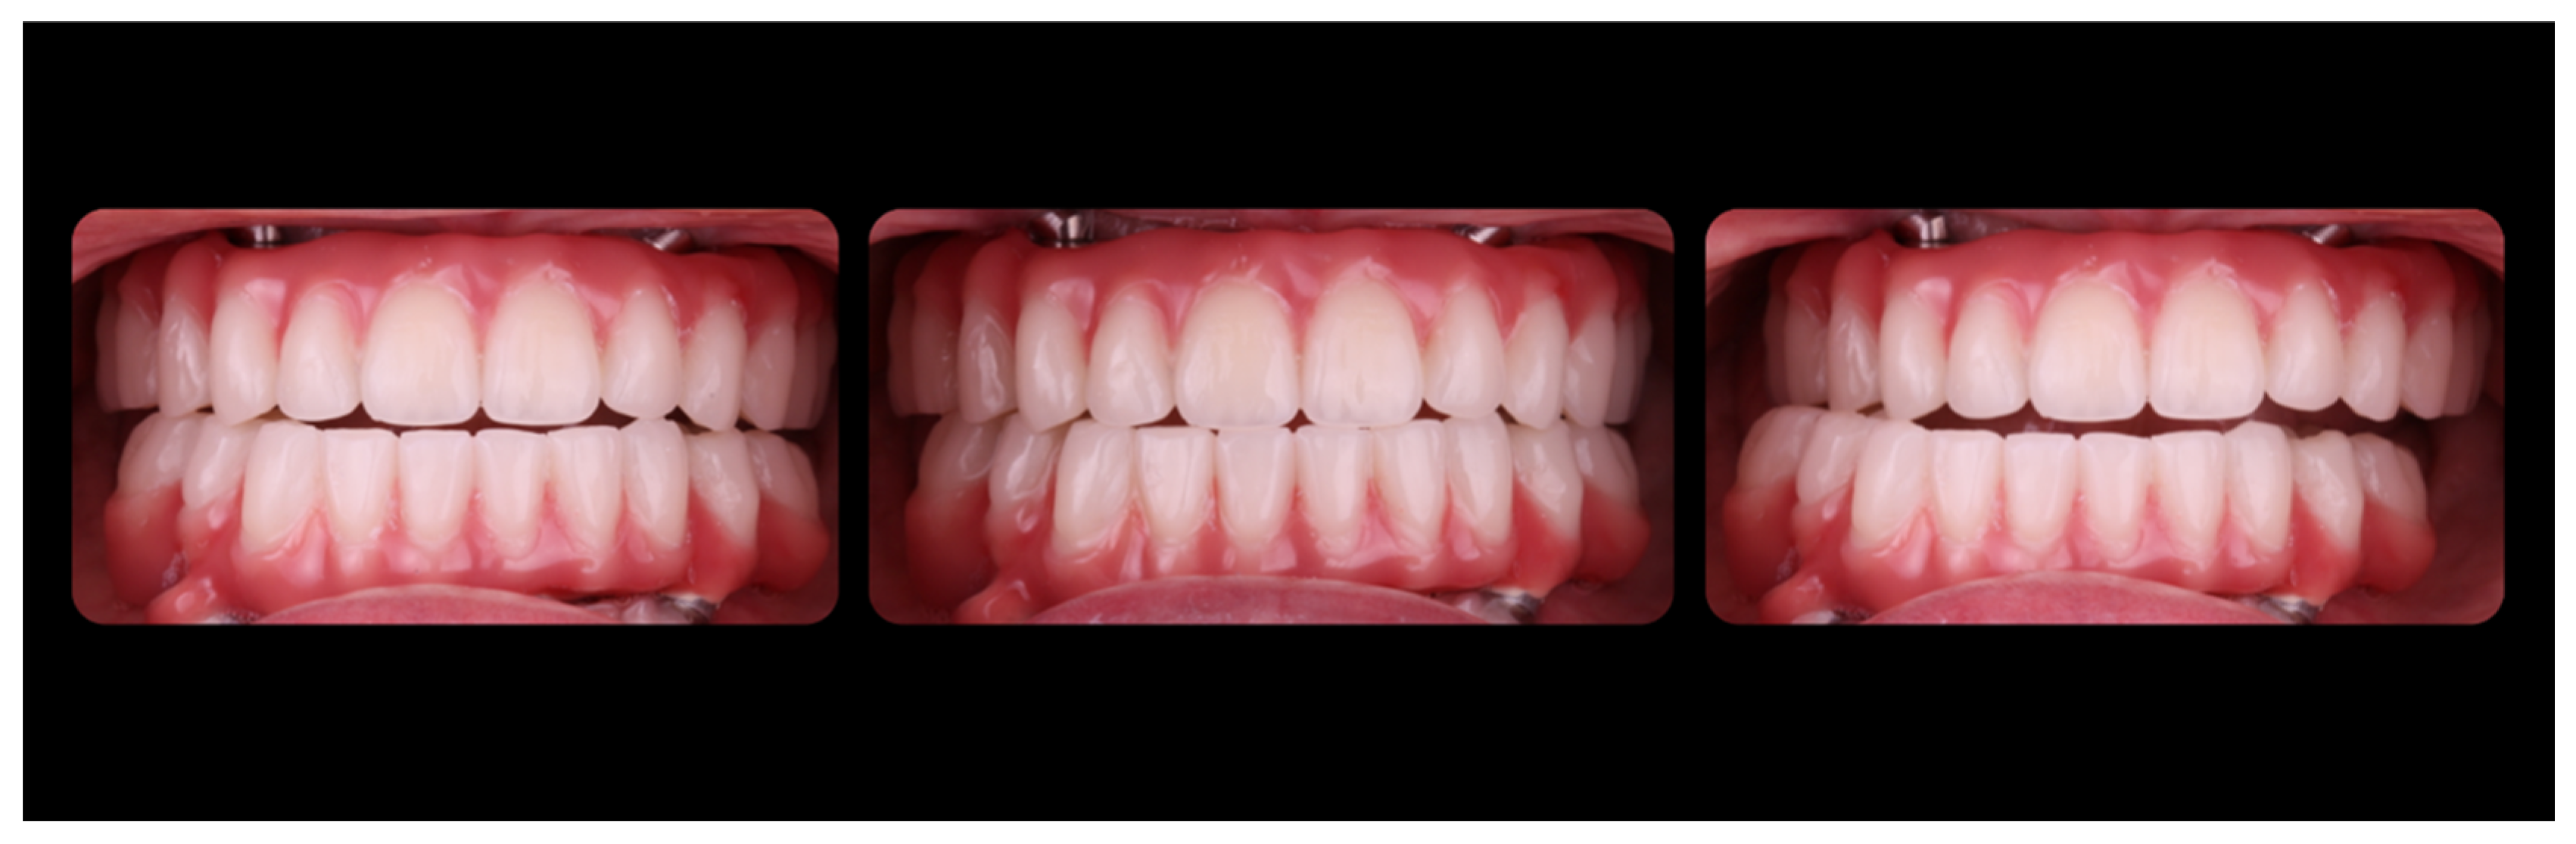

3. Results